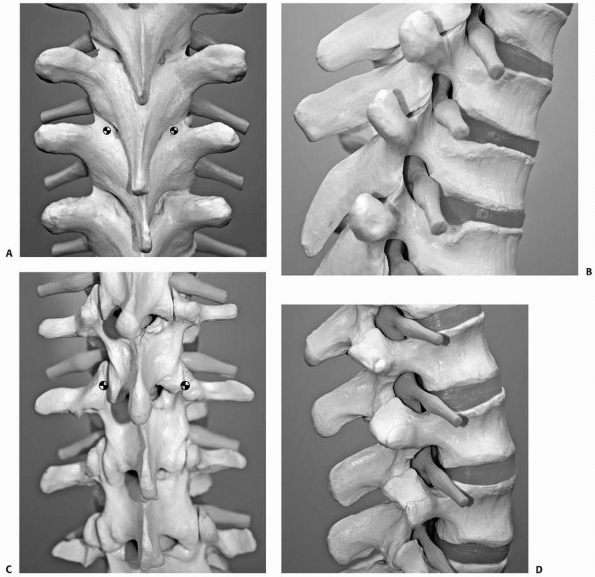

![]() |

FIGURE 19-4 Compression fractures. A. This PA view demonstrates wedging in the coronal plane. B.

The more commonly recognized compression fractures involve wedging primarily in the sagittal plane with loss of anterior vertebral height. |